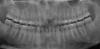

zood Опубликовано 5 февраля, 2010 Автор Поделиться Опубликовано 5 февраля, 2010 (изменено) ..скажите дорогие мои, как тут на снимочках? не все так плохо? Изменено 5 февраля, 2010 пользователем zood Ссылка на комментарий

Bier Опубликовано 5 февраля, 2010 Поделиться Опубликовано 5 февраля, 2010 по снимкам все очень даже не плохо. Можно имплантироваться 100% Ссылка на комментарий

Dr. Surkin Опубликовано 5 февраля, 2010 Поделиться Опубликовано 5 февраля, 2010 Ребят, я конечно понимаю, что КТ это вещь, но в данном случае она избыточна. Облучением избыточна.Под анестезией, да еще откинув лоскут - все можно глазами увидеть, пальцами потрогать, зондом с нёба прозондировать - вот тебе и представление об объеме. Снимки, что сделал пациент - вполне достаточны для дальнейшей работы. По любому надо готовить на вякий случай кость и мембрану, временный абатмент, да идти на операцию, а там по ходу дела решить какая тактика предпочтительнее. Ссылка на комментарий

x3m Опубликовано 5 февраля, 2010 Поделиться Опубликовано 5 февраля, 2010 (изменено) Менять. На панорамном ничего не видно из того, что надо рассмотреть.+100менять подход (мягко говоря)ЗЫ. ортопантомограмма - это двухмерный снимок, по нему невозможно определить кость в объеме (что очень важно для выбора тактики имплантации - чтобы не делать ее "наполовину вслепую"). КТ - это трехмерный снимок, доктор повертит в любой проекции интересующий участок, померяет нужные расстояния с точностью до десятых миллиметра.Короче, ищем КТ и адекватного врача, который и проведет имплантацию. Поищите, здесь на форуме есть врачи из Вашего города. Изменено 5 февраля, 2010 пользователем x3m Ссылка на комментарий